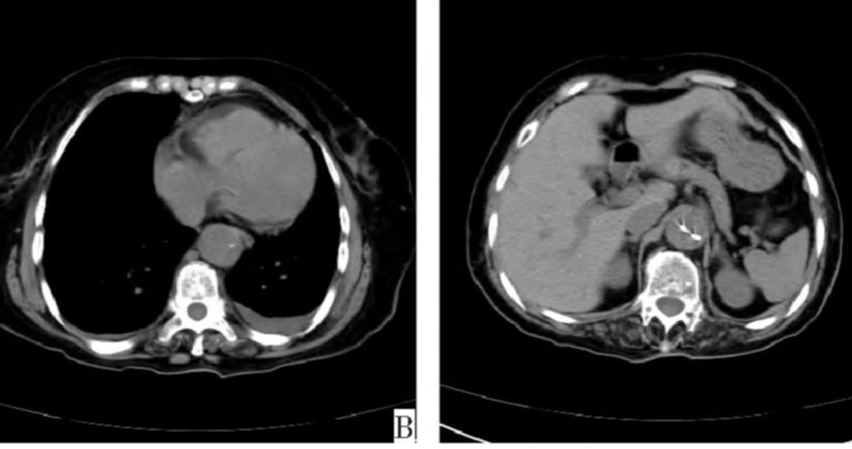

病例3

下图的胸部CT平扫,有什么致命的问题?

图7

仔细一看,主动脉里面有线样阴影!并且,线样阴影两边的密度一高一低!

图8

增强CT一看,主动脉夹层,密度相对高的是流动的血液!

图9

病例4

鲁迅说:孔乙己大约的确已经挂了!

下图的胸部CT平扫,基本上大约肯定可以看到一条线样阴影,将主动脉一分为二!

图10

增强CT一看,主动脉裂开了!

图11